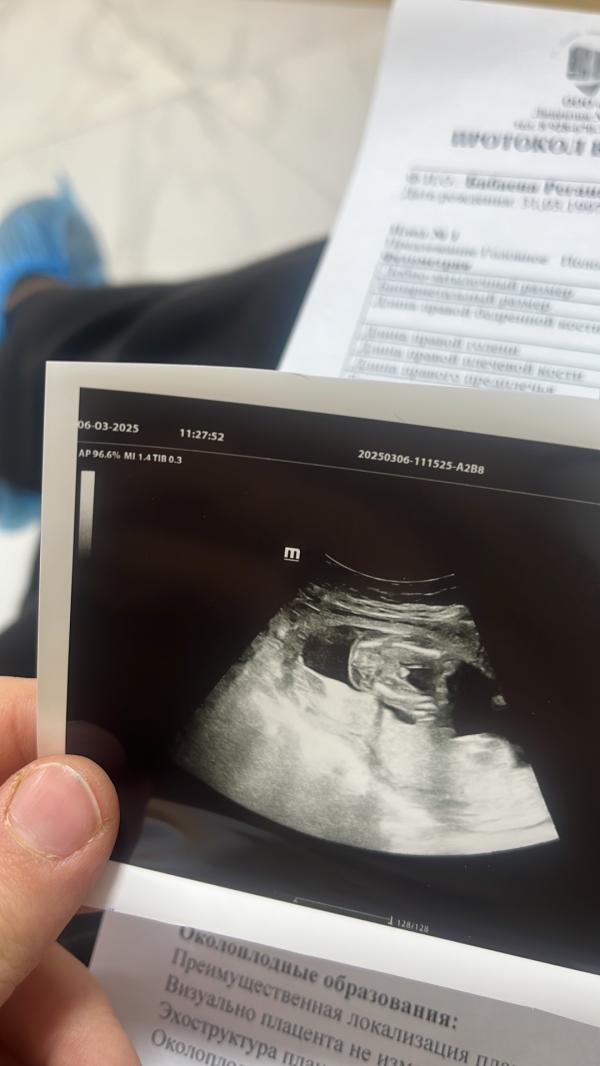

А вот и наш писун 🙈Альхамдулилях 😍❤️мамин Мухаммад

Первый раз у Камиля в Сабуре ,во второй раз в Доктор плюсе тоже сразу сказала мальчик 😄😄🙈😍